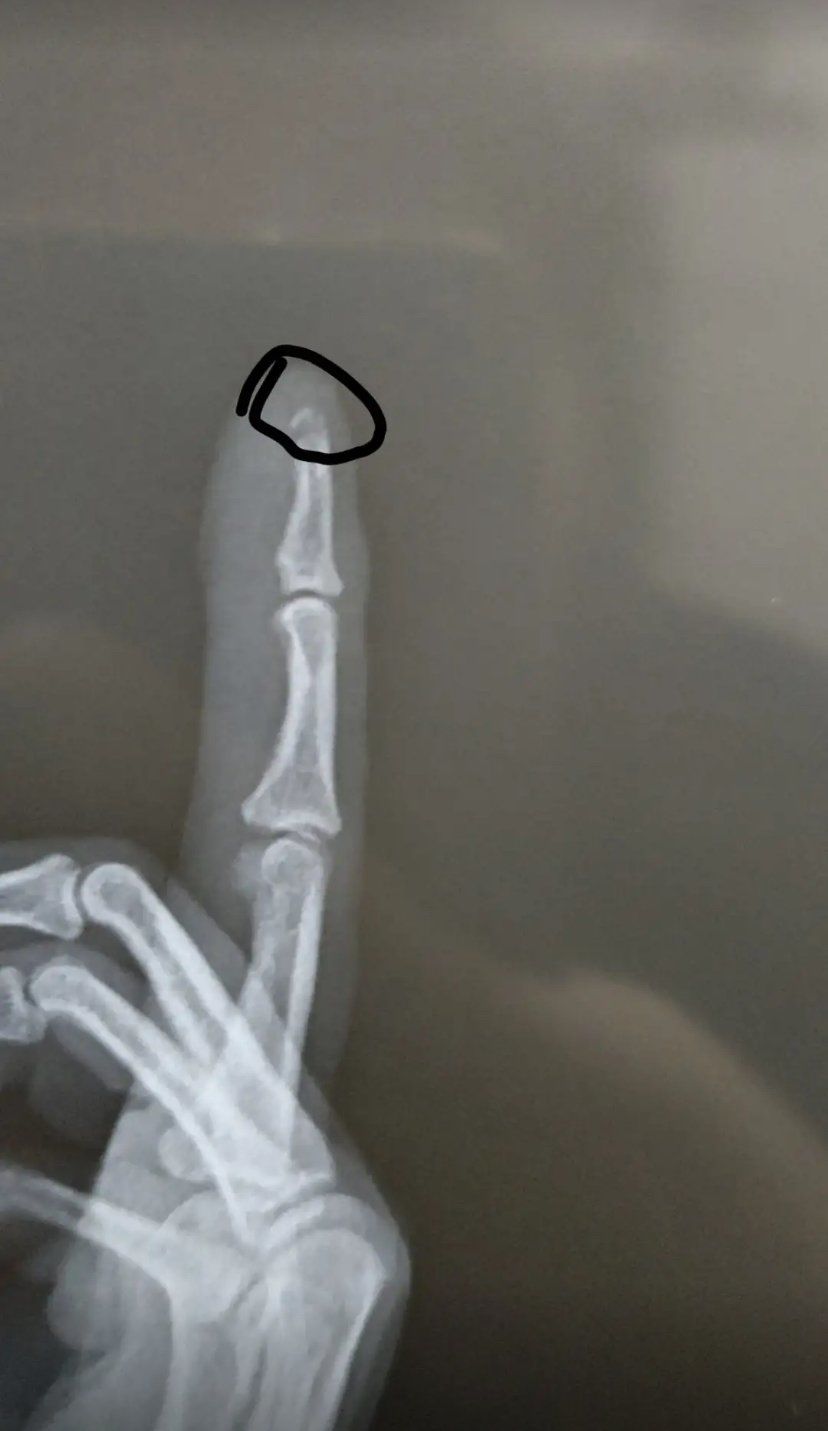

手指轻微骨折

指尖骨头断了,手指骨裂,带薪休假一个月,跟医药费,有懂的可以说说吗?

能保守不手术.#指骨骨折 #保守治疗

拇指近节指骨骨折